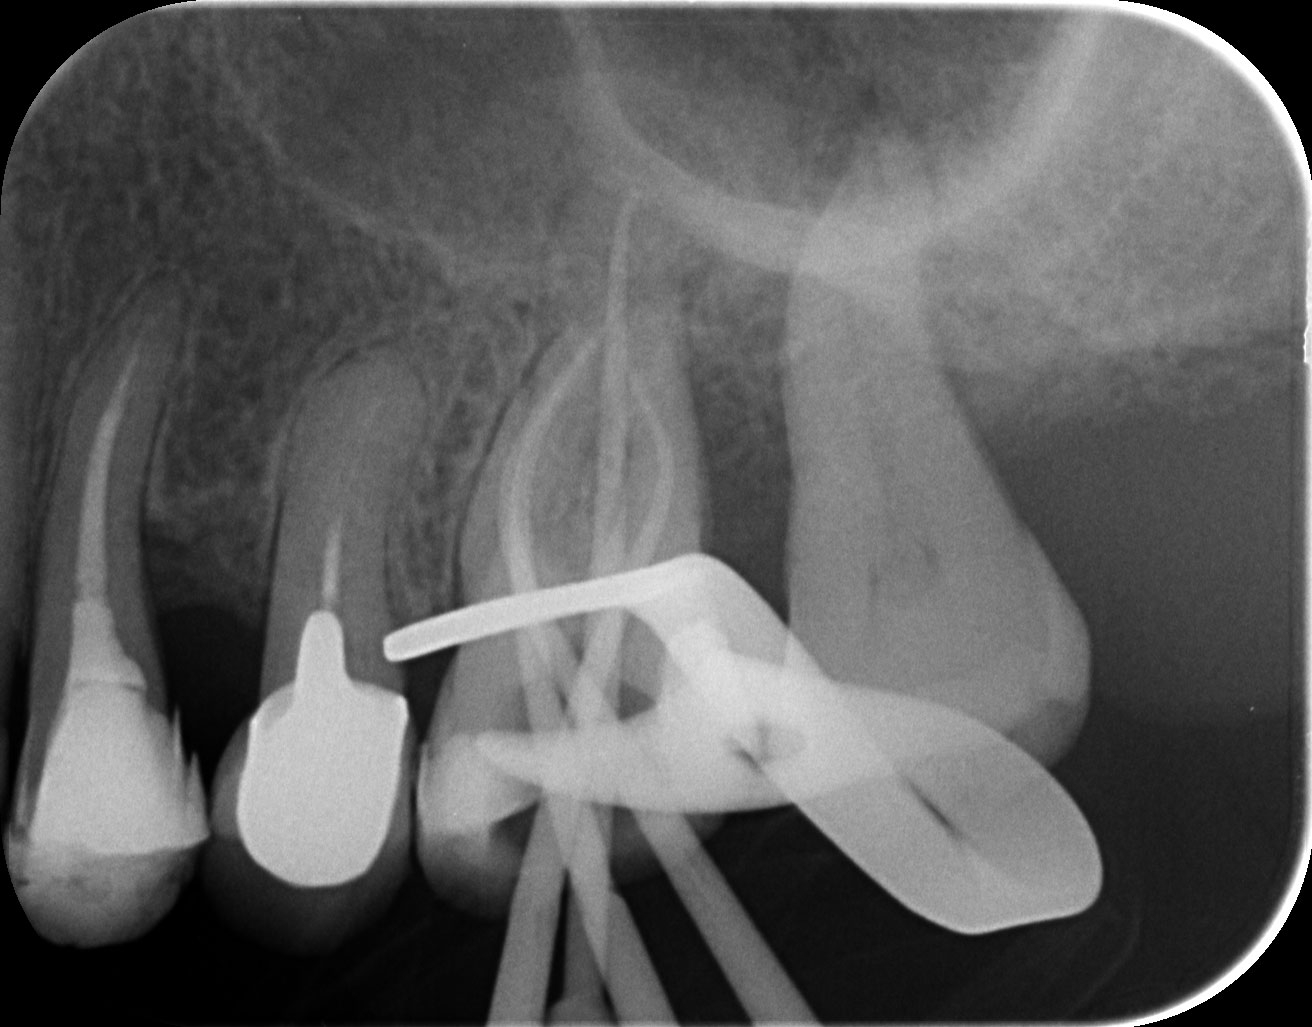

Dantų kanalų gydymas

Pacientas skundėsi pulpitiniais skausmais, pašalinus uždegimo priežastį, sugydžius danties kanalus, skausmas praėjo.